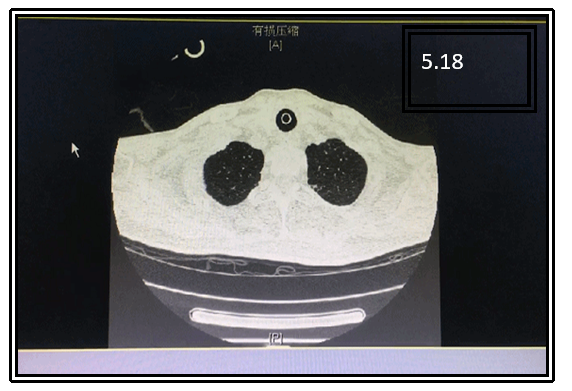

入院时经口气管插管,呼吸机辅助通气,模式SPONT,PS 12 cmH2O,PEEP 5 cmH2O,FiO2 0.3,气道内可吸引出大量黄色Ⅱ度黏痰,意识清楚,精神差。T 36.5℃,P 78次/min,R 18次/min,SpO2 98%,BP 108/62 mmHg。双下肺呼吸音低。胸部CT示双下肺肺不张,右侧包裹性胸腔积液。

患者感染学指标均基本正常(图1);两下肺存在肺不张,右侧包裹性胸腔积液(图2);呼吸力学指标正常(图3)。纤支镜下可见痰液较多,呈黄色,Ⅱ度黏痰(图4)。

图2 患者胸部CT

气道管理效果较为明显,5月28日,患者双下肺肺不张明显改善,且在未使用抗生素的情况下,患者未发生感染(图8)。

图8 患者治疗前后胸部CT对比